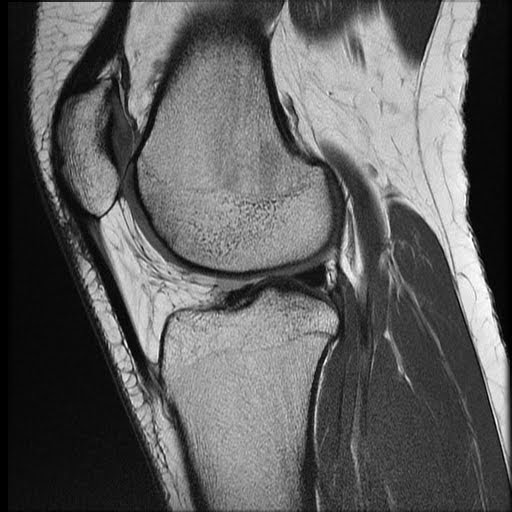

resonance image revealing moderate lateral patellar tilt and What Is Lateral Patellar Tilt Learn about patellar instability, a condition that causes the kneecap to move out of place due to injury, ligamentous laxity or malalignment. It may lead to patellar instability,. Patellar tilt is when the patella is tilted to one side, usually the lateral side, due to tight lateral retinaculum. The lateral patellar tilt (lpt) angle is another distinct and widely used. What Is Lateral Patellar Tilt.